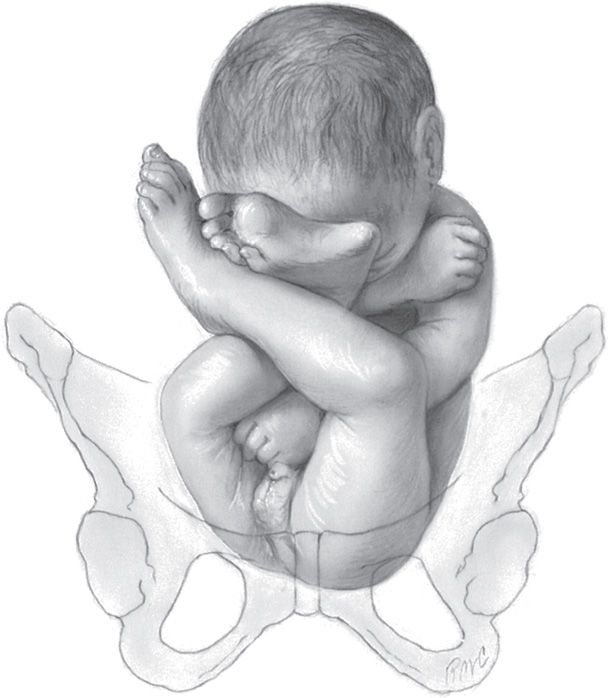

Иконки и символы, связанные с эмбрионом

Раздел: Образы вокруг